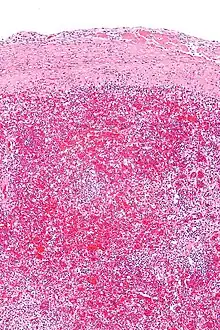

Micrograph of hyaloserositis of the spleen (sugar-coated spleen). H&E stain.

The spleen is commonly affected and often referred to as sugar-coated spleen.[3] The liver and heart are also sometimes affected and referred to as frosted liver (or sugar-coated liver) and frosted heart respectively.[1]